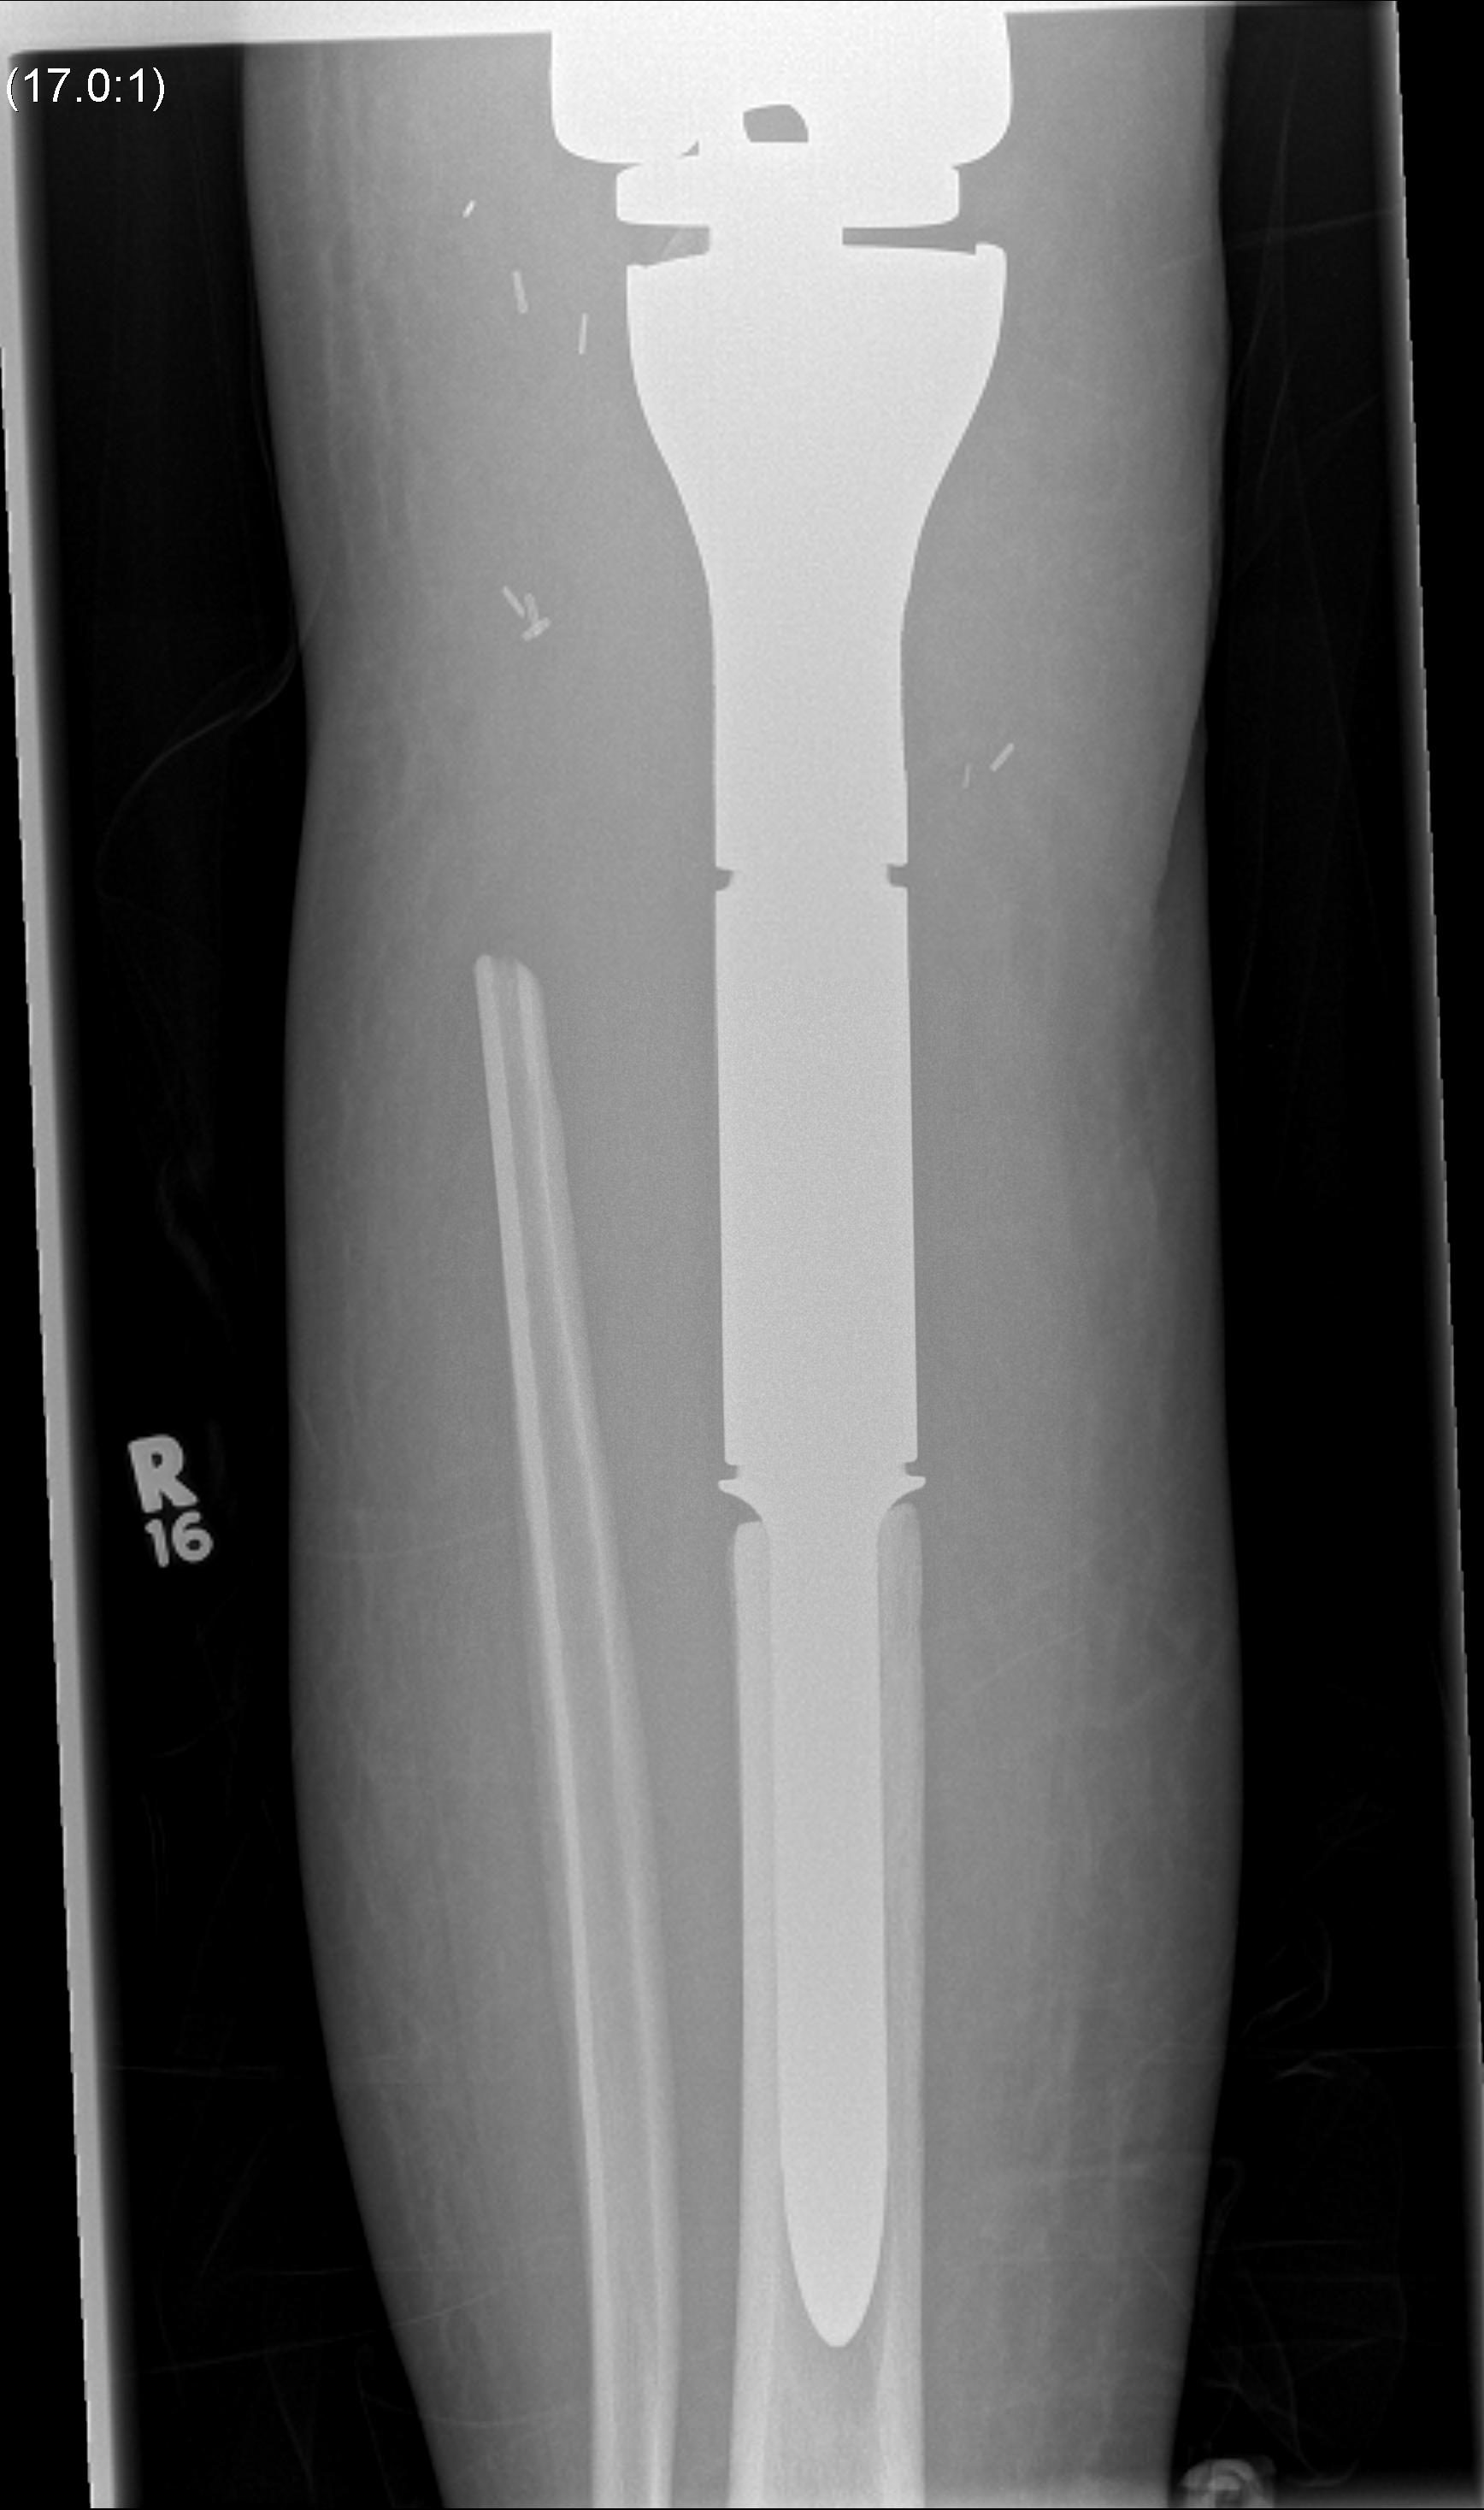

Post proximal tibial osteosarcoma resection